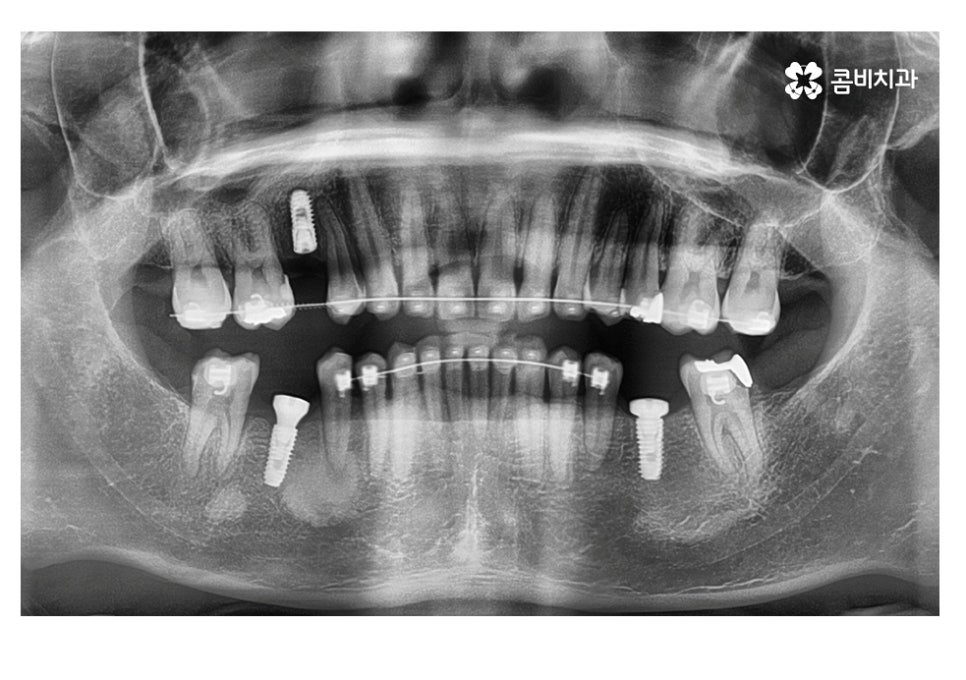

보통 임플란트와 교정을 같이 해야 하는 케이스에는

교정이 끝나기 약 6개월 전에 치료를 하게 되는 경우가 많은데

임플란트 식립 후 뼈가 완전히 굳고 치료를

마무리하기까지 보통 4~5개월 정도 걸리기 때문에

발치와 임플란트의 시술 그리고 교정이 비슷한 시기에

끝날 수 있도록 치료 계획을 세우고 있어요.

임플란트의 수명은 관리를 잘한다면 반영구적인 사용도 가능하지만

20대에 치아를 잃게 되면 보다 장기적으로 관리를 잘해야 하기 때문에

치아 상실 원인을 잘 파악하고 지속적인 사후관리에 신경 써야 한다는 점도

잘 참고하셔서 치과 선택에 보다 신중해야 할 수 있어요.